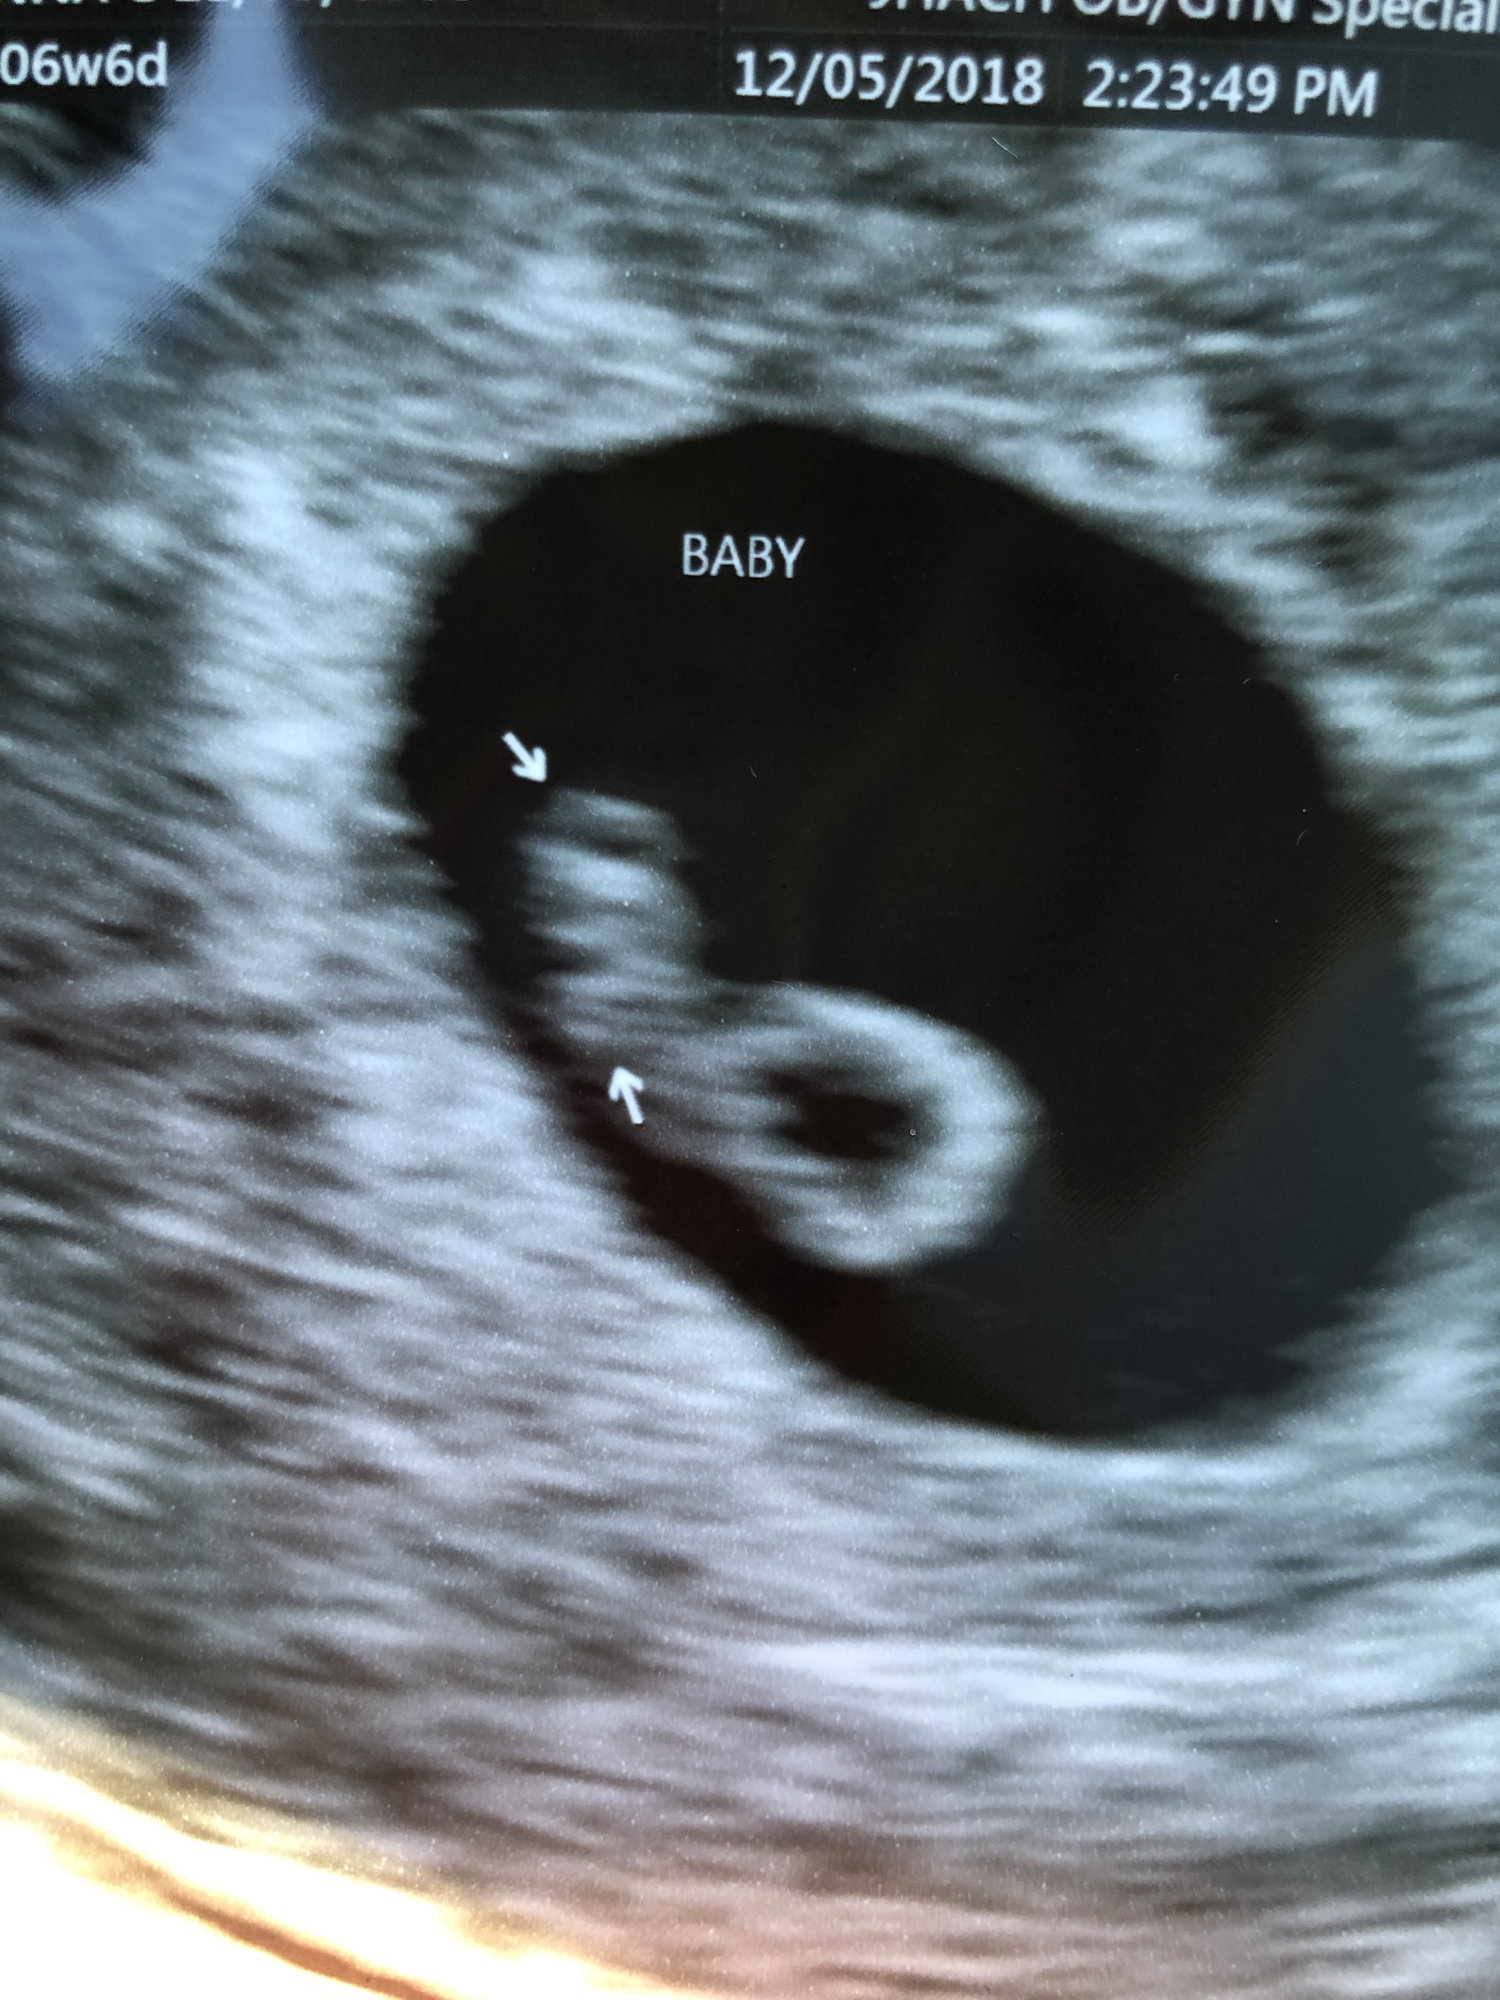

Hi everyone! My EDD is 7/1/2019, so I’m not sure if I’ll be here or in June. Here is our ultrasound photo from 8 weeks (transvaginal) a couple weeks ago. Heartbeat was 172bpm. Baby is the blob on the upper right, facing away.

Here is our ultrasound photo from 8 weeks (transvaginal) a couple weeks ago. Heartbeat was 172bpm. Baby is the blob on the upper right, facing away.